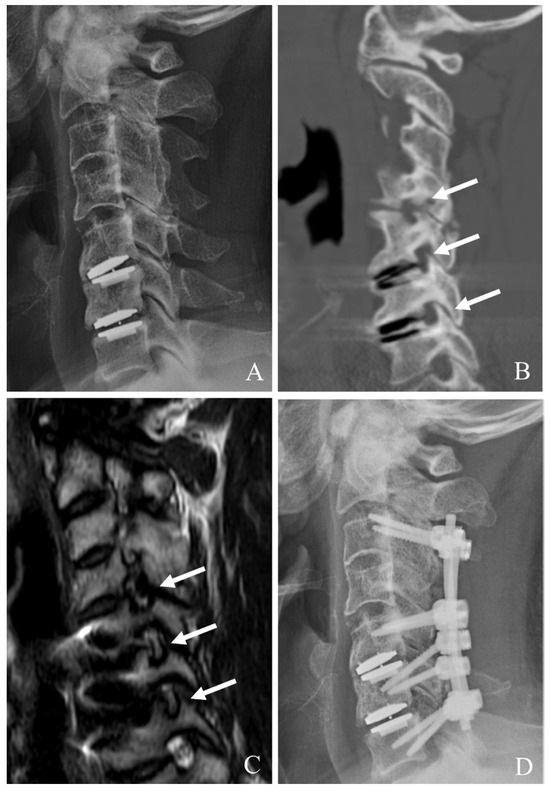

5.1. Conversion to ACDF or ACCF

Conversion to ACDF is the most common approach when index-level failure is associated with severe heterotopic ossification (HO), significant subsidence, or mechanical instability [22,23,24,25,26]. This method involves an anterior approach to remove the failed prosthesis, debridement of scar tissues and HO, and neural decompression such as posterior longitudinal ligament (PLL) resection and uncoformaminotomy. An interbody fusion is then performed using appropriate graft material, augmented by anterior plating to achieve stability. ACDF provides robust stabilization and high fusion rates (often >90%). It can reliably alleviate symptoms (Figure 1). However, it sacrifices motion at the index level, potentially predisposing patients to further ASD.

Figure 1. Plain X-rays (A,B), magnetic resonance image (C), and computed tomography (D) showing cervical disc arthroplasty at C5–6 and C6–7 with severe foraminal stenosis and posterior osteophytes (white arrows). The patient underwent removal of C5–6 and C6–7 prosthesis and revisional anterior cervical discectomy and fusion (EH).